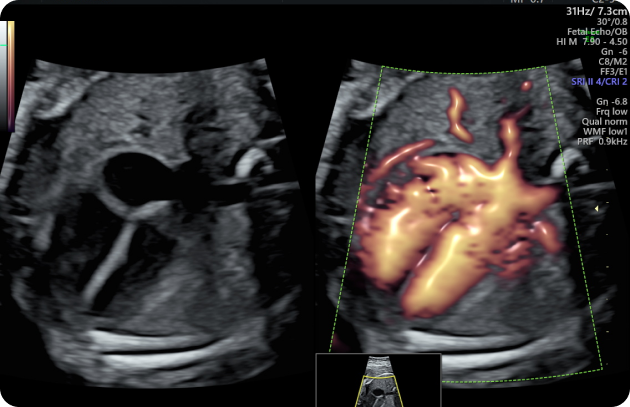

Fetal echocardiography is a specialized ultrasound test used to examine the heart of a developing baby during pregnancy. This scan focuses specifically on the structure and function of the fetal heart, helping doctors evaluate how the heart chambers, valves, and blood vessels are forming and working.

The test provides detailed images of the baby’s heart and helps detect possible congenital heart defects or abnormalities. Early diagnosis of heart conditions allows doctors to plan appropriate monitoring, treatment, and delivery care if necessary.

Fetal echocardiography is usually performed by specialists using advanced ultrasound technology to obtain a detailed assessment of the baby’s cardiovascular system.

Detailed Heart Examination: The sonographer carefully evaluates the four chambers of the fetal heart, the heart valves, and the major blood vessels.

Blood Flow Assessment: Doppler ultrasound may be used to observe the direction and speed of blood flow within the heart.

Heart Measurements: The size, rhythm, and overall function of the heart are assessed to ensure normal development.

Detection of Abnormalities: The scan can help identify certain heart defects, rhythm disturbances (arrhythmias), or structural abnormalities.